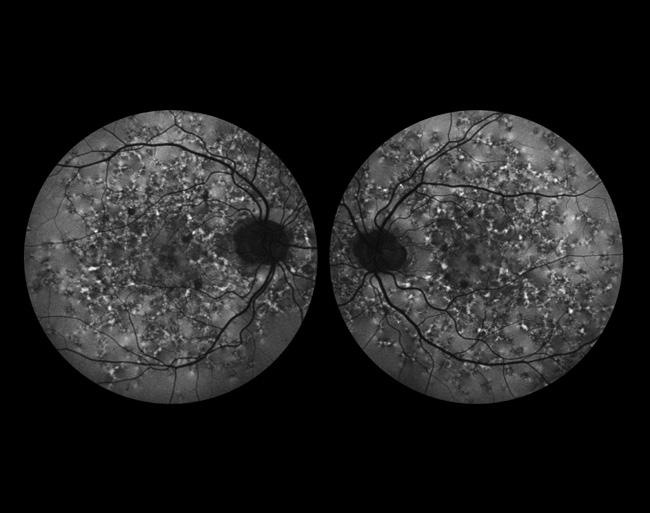

Cross Categories

AZOOR

Dena Harris, CRA

University of Michigan Kellogg Eye Center

Ann Arbor, Michigan